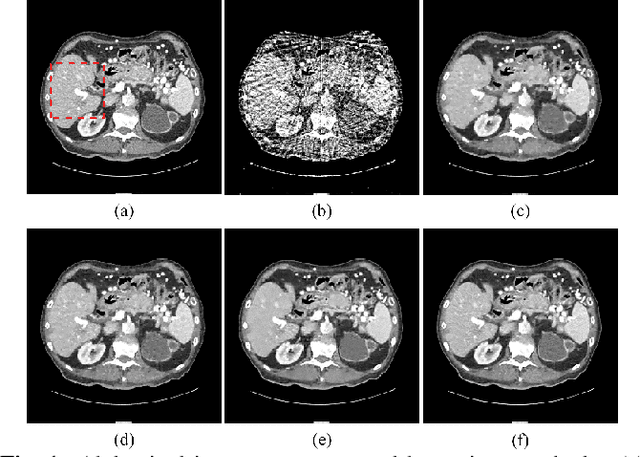

Traditional dictionary learning based CT reconstruction methods are patch-based and the features learned with these methods often contain shifted versions of the same features. To deal with these problems, the convolutional sparse coding (CSC) has been proposed and introduced into various applications. In this paper, inspired by the successful applications of CSC in the field of signal processing, we propose a novel sparse-view CT reconstruction method based on CSC with gradient regularization on feature maps. By directly working on whole image, which need not to divide the image into overlapped patches like dictionary learning based methods, the proposed method can maintain more details and avoid the artifacts caused by patch aggregation. Experimental results demonstrate that the proposed method has better performance than several existing algorithms in both qualitative and quantitative aspects.